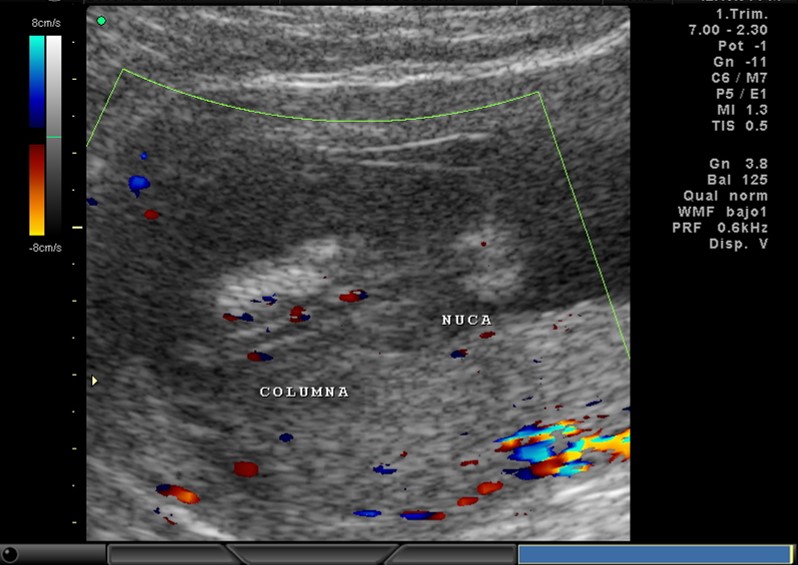

2D, CABEZA, COLUMNA, COSTILLAS

2D Y COLOR, NUCA, CANAL RAQUIDEO, CORAZON Y VASOS